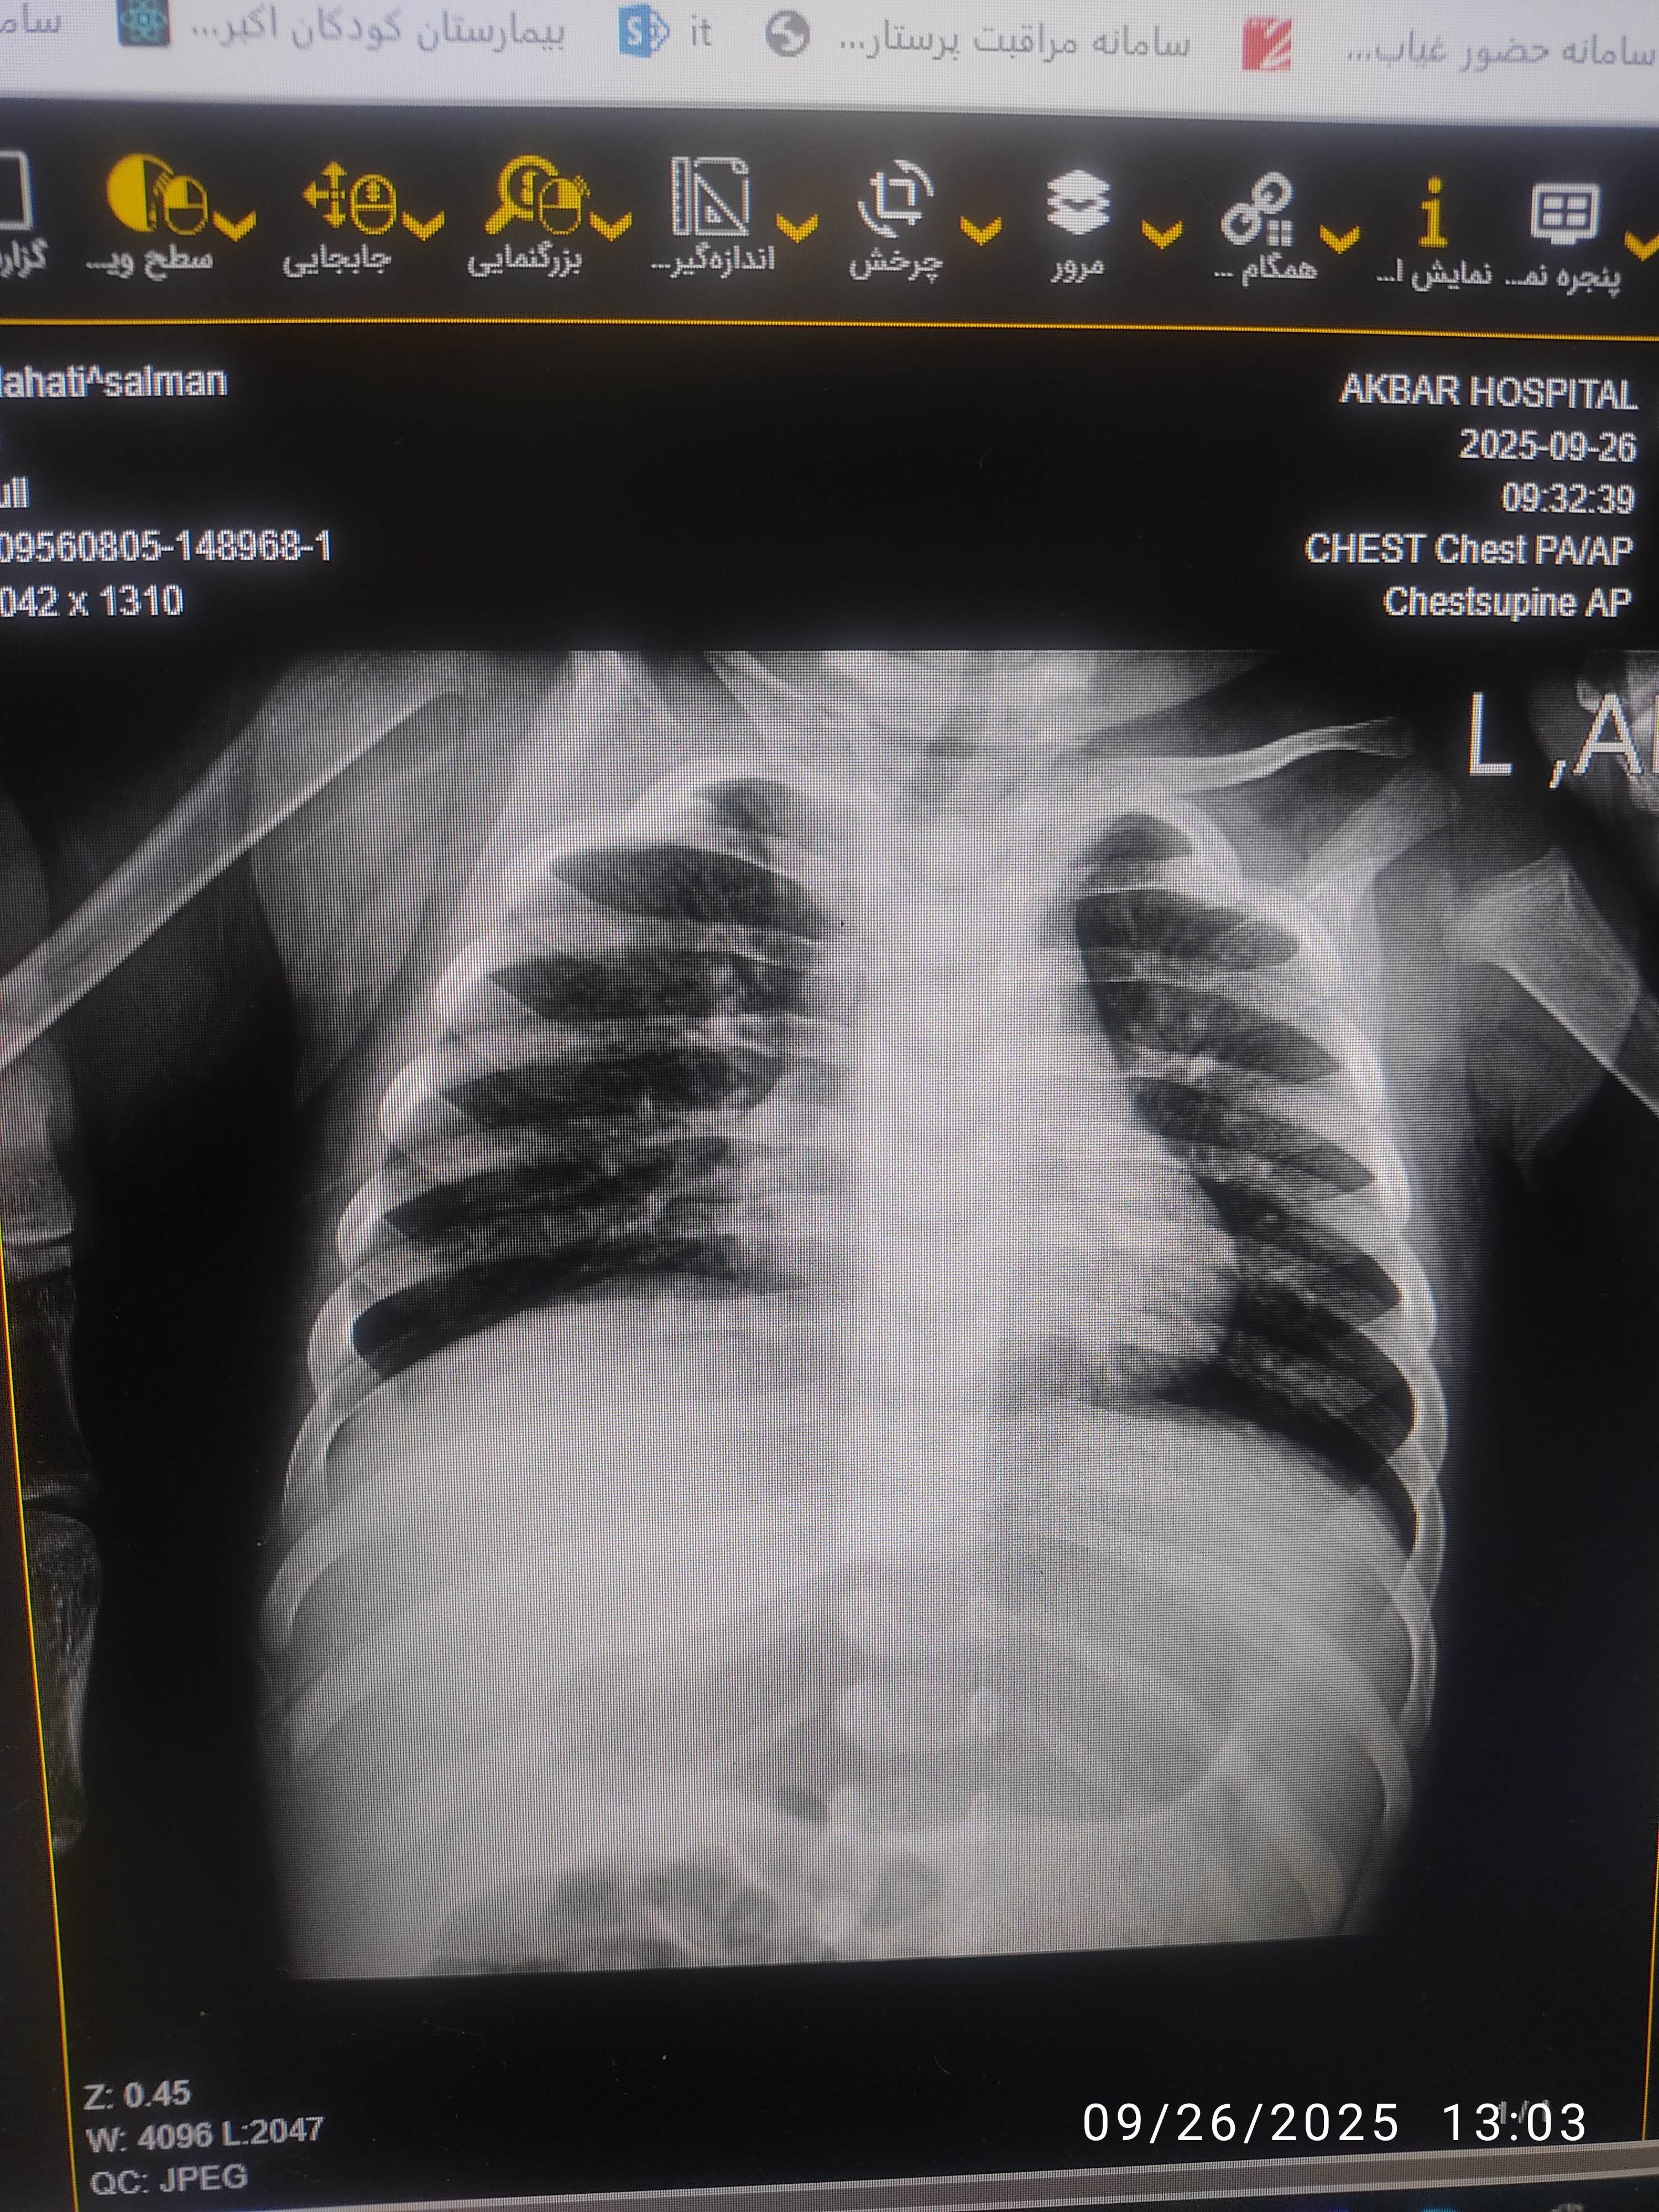

سمع ریه : کراکل در قواعد ریه

تاکی پنه ، کراکل در قواعد ریه

پنومونی ( باکتریال ، قارچی ، ویروسی )

cbd diff, crp , blood culture, UA, bun cr, ABG , CXR